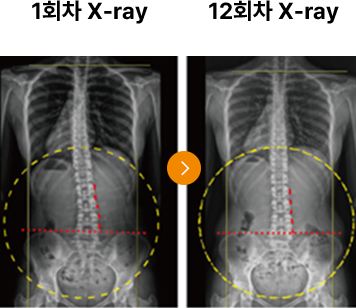

통증을 유발하던 골반 틀어짐과, 일자목 증상이 도수치료 후 본래의 자리로

돌아옴으로 통증을 완화시켜줍니다.